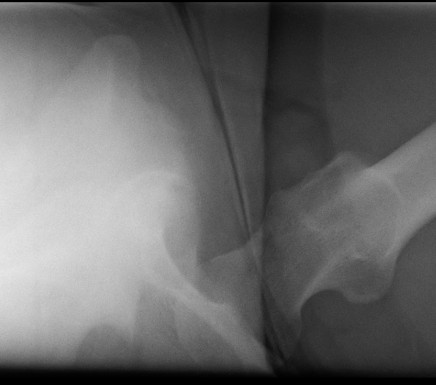

Posterior dislocation

- leg shortened, flexed, adducted & internally rotated

- head small on xray

Anterior dislocation

- leg short and externally rotated

- head larger on xray